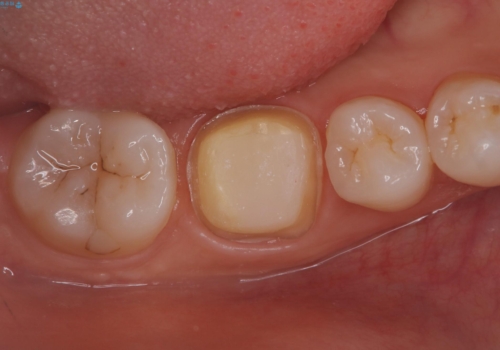

ファイバーコア 2万円

仮歯 1万円